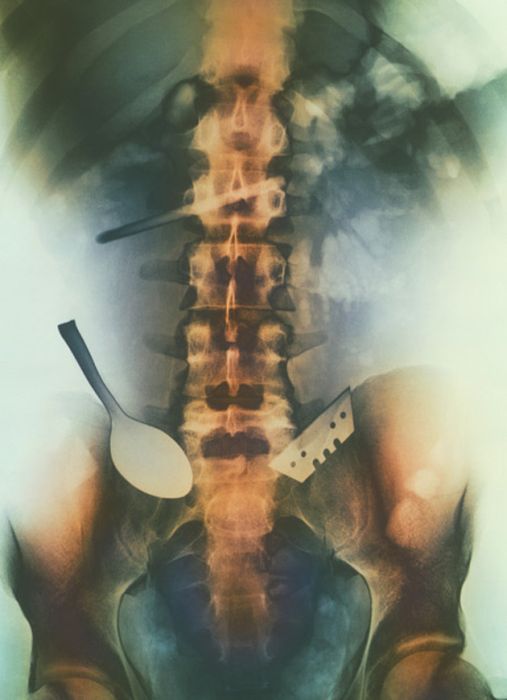

Рентгеновские снимки людей, которые умудрились сами или с чужой помощью разместить внутри своего организма разные посторонние предметы. От вилок и ножей до пуль и бензопилы (!!!). По этическим соображениям обычные снимки таких травм и повреждений выкладывать нельзя, зато рентгеновские можно – на них травмы видны достаточно условно, хоть и очень понятно.